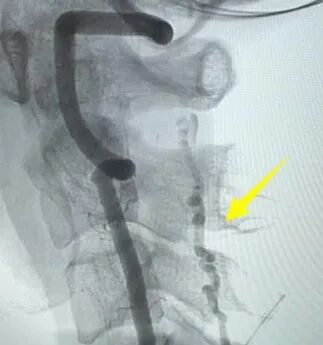

為進(jìn)一步明確診斷,神經(jīng)外科負(fù)責(zé)人景英朝主任帶領(lǐng)團(tuán)隊為患者進(jìn)行了脊髓血管造影,術(shù)中明確“頸5水平硬脊膜動靜脈瘺”!至此,幕后“元兇”終于浮出水面,病因精確鎖定為一種罕見疾病——硬脊膜動靜脈瘺。

血管造影檢查